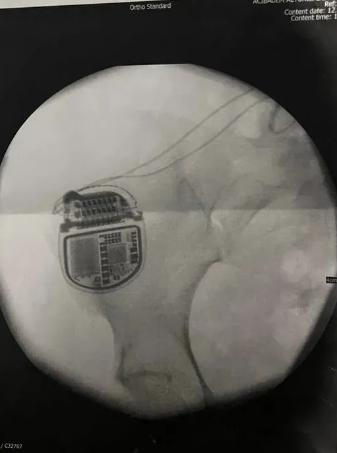

Ameliyatın ardından altıncı ayda sol bacağındaki felç durumunun iyileştiğini söyleyen Z.T. açıklamasının devamında, "Asıl problem sağ bacağımda olduğu için şu an ikinci yılımdayım ve bu iki yıla rağmen hala iyileşmedi ve ben omurgamda ömür boyu pile mahkum bırakıldım. Bu piller neredeyse servet değerinde ve fiyatı 1 buçuk milyon lira. Her 5, 6 yılda bir bu pillerimin sökülüp takılması gerekiyor. Bülent Cihantimur yüzünden ömür boyu pillere mahkum bırakıldım. Bileklerimde felç ve düşük ayak sendromu kaldı. Ölümcül ağrılarla yaşamak zorundayım. 9 kere ameliyat oldum. Bunlardan 6’sı omurga 3’ü de bacaklarımdan.

Fizik tedavi uygulandı bu gördüğünüz halim benim son iki yıldaki en iyi halim. Benim omurgamdan enseme kadar kablolar var, kalçamda cihaz var. Bülent Cihantimur’un elini kolunu sallayarak özgürce sokaklarda dolaşmasını istemiyorum. Benim gibi birçok mağdur var. Kendisinin çok kötü bir sicili var.